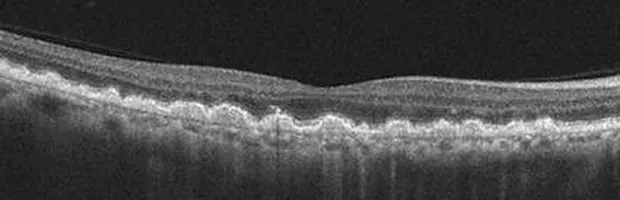

The normal macula is flat but with a slight dip at very center (known as the fovea). The deepest layer of the retina, the retinal pigmented epithelium (RPE) is smooth and even (orange band).

As people age, the vitreous gel often eventually pulls away from the retina. This posterior vitreous detachment (PVD) is a common cause of new floaters or flashes of light. These symptoms can mimic retinal tear and/or detachment, so a prompt appointment is recommended if ever encountered, in order to rule out those conditions. Typically there is a clean separation of the vitreous membrane and the retina at the time of PVD, but in this photo above there has remained an area of persistent vitreo-macular traction (VMT). This will cause decreased/distorted vision until it releases. When it does release the vision may return to near normal levels, or in some cases it will proceed to the formation of a macular hole (See photo below).